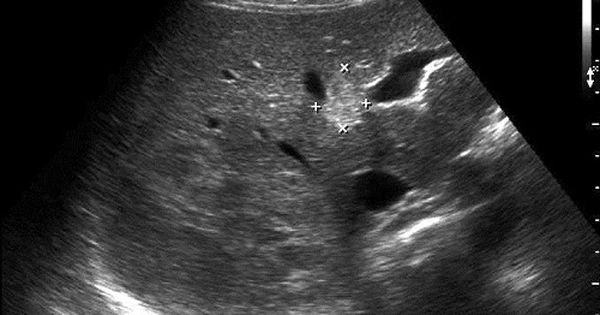

Đã nhập viện với triệu chứng vàng da, vàng mắt và đau bụng, người đàn ông này bị phát hiện có sán lá gan đang hoạt động trong cơ thể Đây là một trường hợp đáng lo ngại và cần được điều trị kịp thời để...